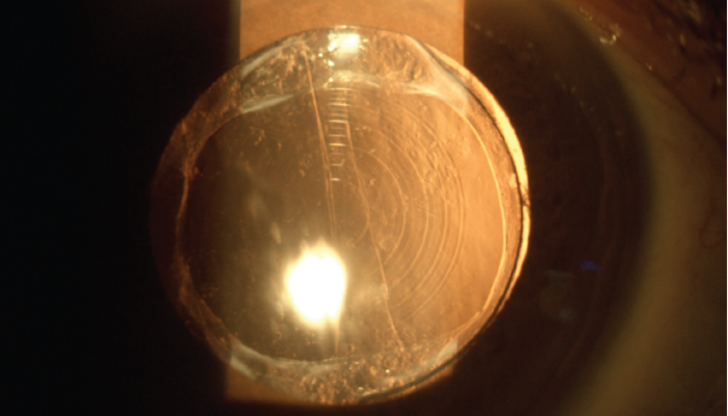

Premium lens cataract surgeries have transformed vision correction for millions globally, yet complications such as glare, halos, and blurry vision can leave some patients disappointed. Dr. Arun C. Gulani, a world-renowned eye surgeon, offers a groundbreaking, non-invasive approach to addressing these challenges by optimizing the cornea to work in harmony with the implanted lens. Learn how this innovative solution restores vision and exceeds patient expectations, all without going back under the knife.

Dr. Gulani’s method focuses on corneal optimization rather than invasive lens replacement, providing a non-surgical, effective solution for post-surgery vision complications.

Premium lens implants are just one ingredient in the overall “vision recipe.” By precisely reshaping the cornea to align with the lens, Dr. Gulani restores clarity while maintaining the integrity of the original surgery.